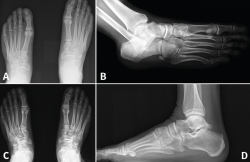

Figura 3. Caso 2. A: radiografía preoperatoria anteroposterior con diástasis en la articulación de Lisfranc; B: radiografía oblicua preoperatoria; C: corte de tomografía computarizada oblicuo.

Se trata de una mujer de 26 años atendida en urgencias tras un traumatismo con torsión del pie. Se realiza radiografía y TAC, objetivando diástasis de 9 mm sin lesión ósea (Figura 3) y diagnosticando, por tanto, lesión sutil de Lisfranc.